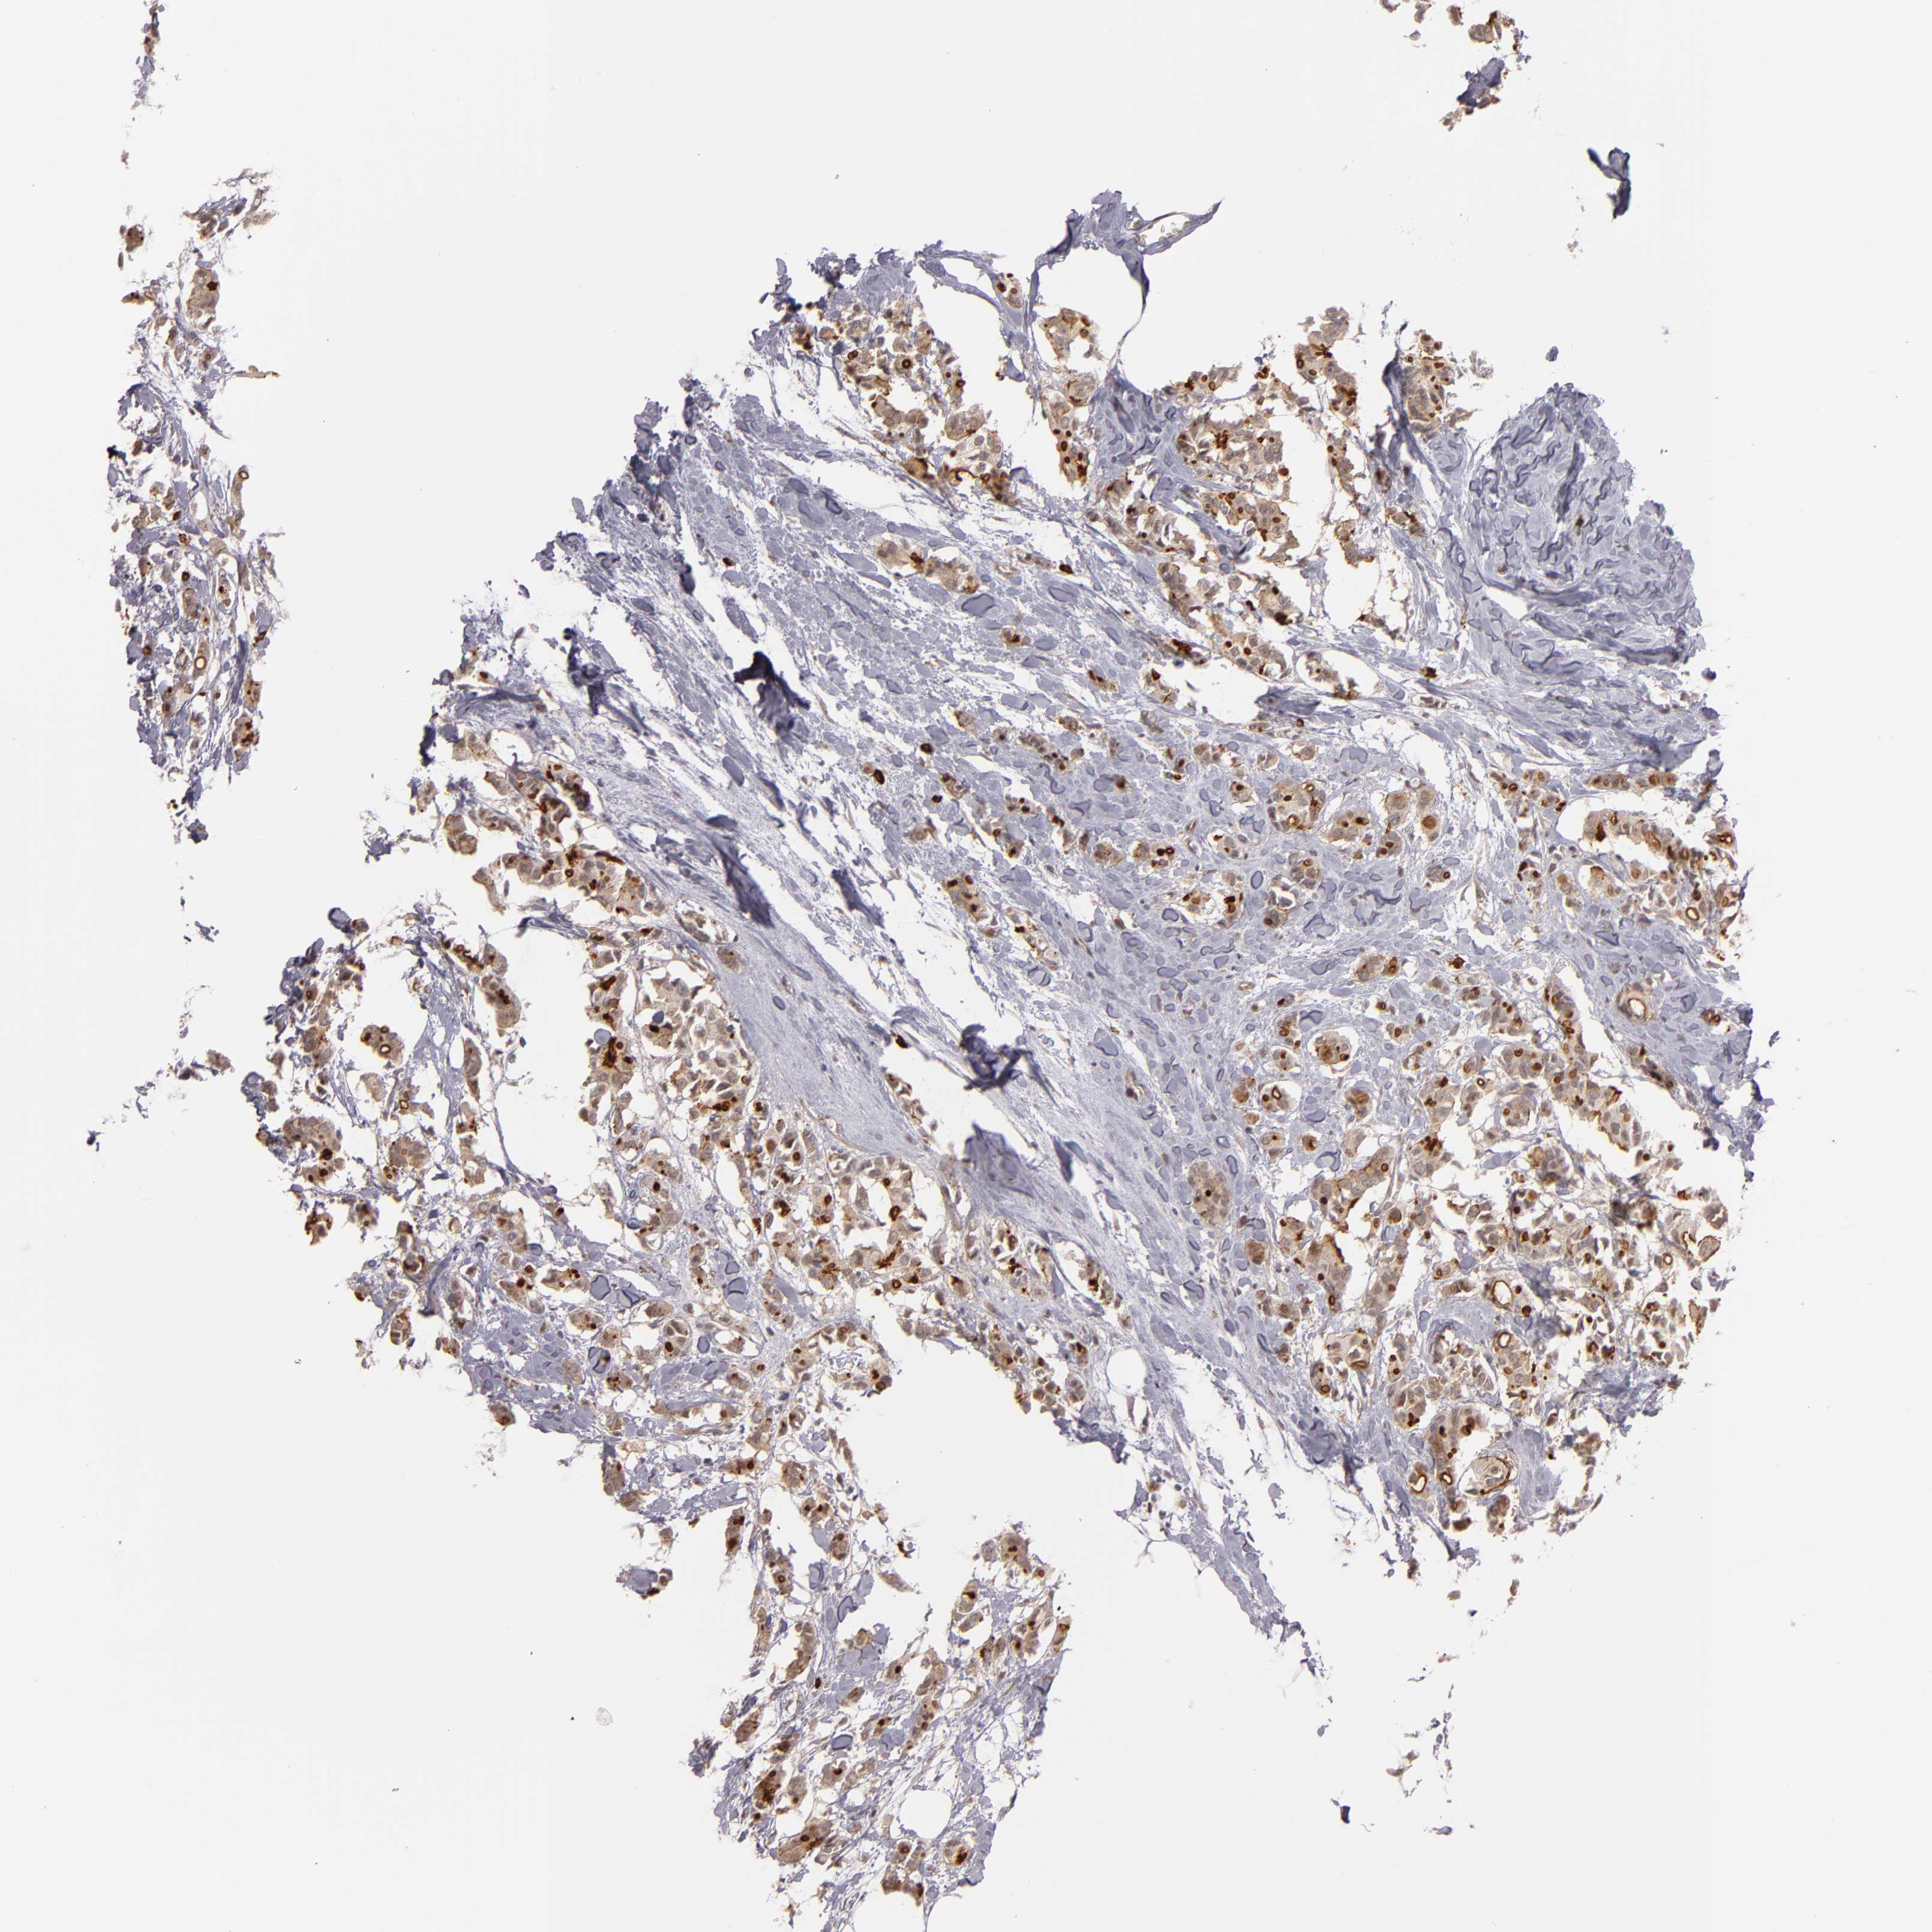

CANCER BREAST CANCER Show tissue menu

BRCA TCGA BRCA VALIDATION PROTEIN EXPRESSION